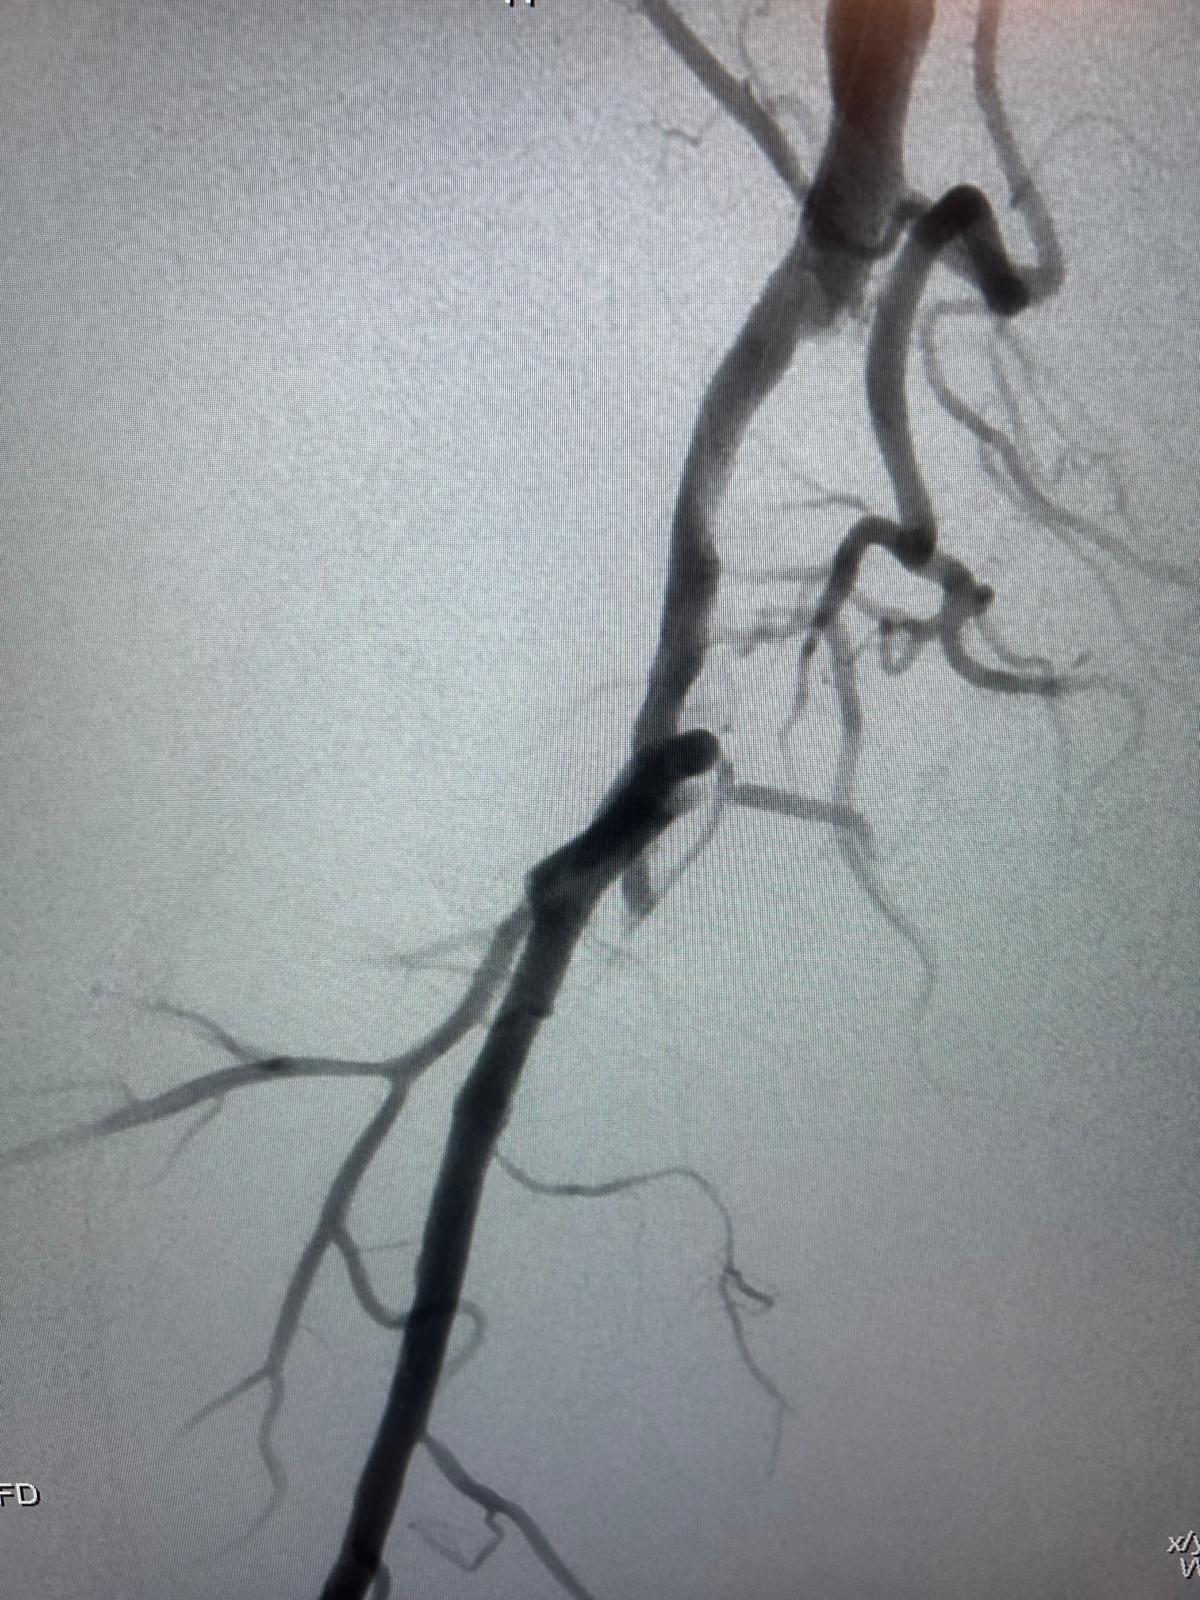

Imagerie pré-opératoire

Angio-TDM montrant une occlusion longue, intra-stent, hypodense, à l'origine de l'artère fémorale superficielle droite, mal compensée par la collatéralité fémorale profonde.

En distalité, belle artère tibiale postérieure unique assurant la vascularisation du pied.

Résultat

Excellent résultat anatomique immédiat au contrôle artériographique per-opératoire.

Respect de la perméabilité de l'ostium de l'artère fémorale profonde et de ses collatérales au niveau de la jonction fémoro-poplitée.

Aucune embolisation distale per-opératoire constatée au niveau des artères de jambe et du pied.

Très bonne revascularisation clinique du pied et excellent pouls tibial postérieur droit.